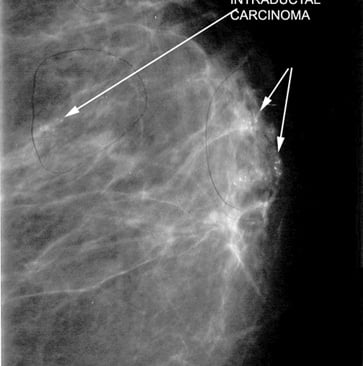

Mikrokalsifikasyonlar: LR (+) 15.0. (Özellikle pleomorfik/dallanan tipteyse)

Luminal A Dominansı: Spiküle (kenarları ışınsal uzantılı) kitlelerin %71'i Luminal A alt tipi olarak sınıflandırılmıştır.

Olasılık Oranı (Odds Ratio): Luminal A alt tipindeki kitlelerin, diğer alt tiplere oranla mamografide spiküle görünüm sergileme olasılığı 10.3 kat daha fazladır (p < 0.001).

Biyobelirteç Korelasyonu: Spiküle görünümün en güçlü öngörücüleri Düşük Ki67 indeksi (< %14) ve HER2 negatifliğidir. Hormon reseptör (ER/PR) pozitifliği de ilişkili bulunmuştur ancak etkisi Ki67 ve HER2 kadar baskın değildir.

Mamografide görülen spiküle kitle, invaziv meme kanserinin Luminal A alt tipi için güçlü bir radyolojik belirteçtir. Bu korelasyonun temelinde tümörün düşük proliferatif aktivitesi (Ki67) ve HER2 gen ekspresyonunun olmaması yatar. Bu veriler, "spiküle kitle" verisinin, biyopsi öncesi Luminal A olasılığını (prior probability) belirgin şekilde yükselttiğini kanıtlamaktadır.